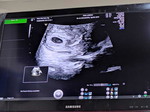

#firstbaby kehamilan pertama 8 minggu mabok nya ampun ampunan. Apalagi ada maagh Apa bunda bunda ada yang ngalamin hal yg sama?